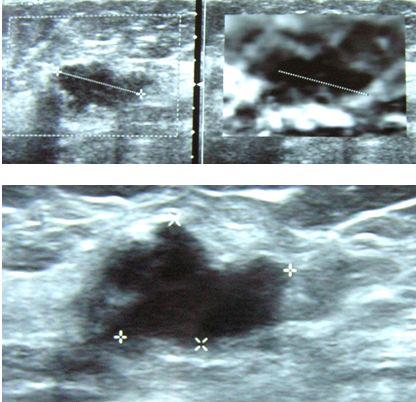

TGS was 66 years old. In January 2012, she had an ultrasound and this is the picture showing a lump in her left breast at 2 o’clock position.